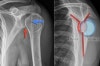

X-ray : 어깨 후방 탈구(Posterior shoulder dislocation)

영상 검사

AP view에서는 팔이 내회전 상태로 인해 상완골 근위부가 백열 전구처럼 보이는 소견(light bulb sign)을 제외하면 정상 소견을 보여 오진되는 경우가 종종 있습니다.

Lateral view나 axillary view에서 상완 골두의 후방 탈구를 관찰할 수 있습니다.